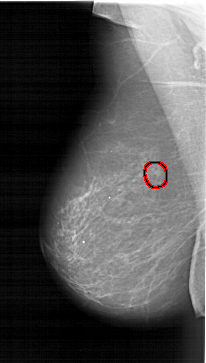

A_1261_1.RIGHT_CC

RIGHT_CC LINES 5551 PIXELS_PER_LINE 3241 BITS_PER_PIXEL 12 RESOLUTION 43.5 OVERLAY

FILE: A_1261_1.RIGHT_CC.OVERLAY

TOTAL_ABNORMALITIES 1

ABNORMALITY 1

LESION_TYPE MASS SHAPE LOBULATED MARGINS CIRCUMSCRIBED

ASSESSMENT 4

SUBTLETY 5

PATHOLOGY MALIGNANT

TOTAL_OUTLINES 1

BOUNDARY